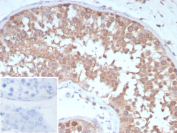

Immunohistochemistry analysis of CD202b / TIE2 antibody in human testis tissue (clone TEK/9411). FFPE human testis sections demonstrate HRP-DAB brown cytoplasmic and membranous staining in cells within seminiferous tubules, consistent with TEK receptor tyrosine kinase expression in vascular and interstitial compartments. Endothelial cells associated with microvasculature show distinct membranous brown chromogenic signal, while surrounding stromal elements display minimal staining. The inset shows PBS used in place of primary antibody as a secondary antibody negative control, confirming absence of specific brown signal. Heat induced epitope retrieval was performed in 10 mM Tris with 1 mM EDTA, pH 9.0, by heating tissue sections at 95oC for 45 minutes followed by cooling at room temperature for 20 minutes prior to antibody incubation.